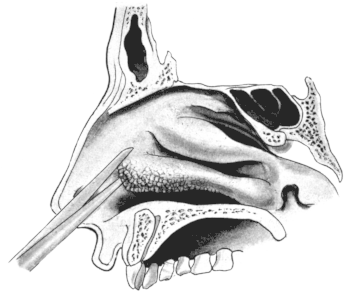

| 345. | Catheterizing the Sphenoidal Sinus | 654 |